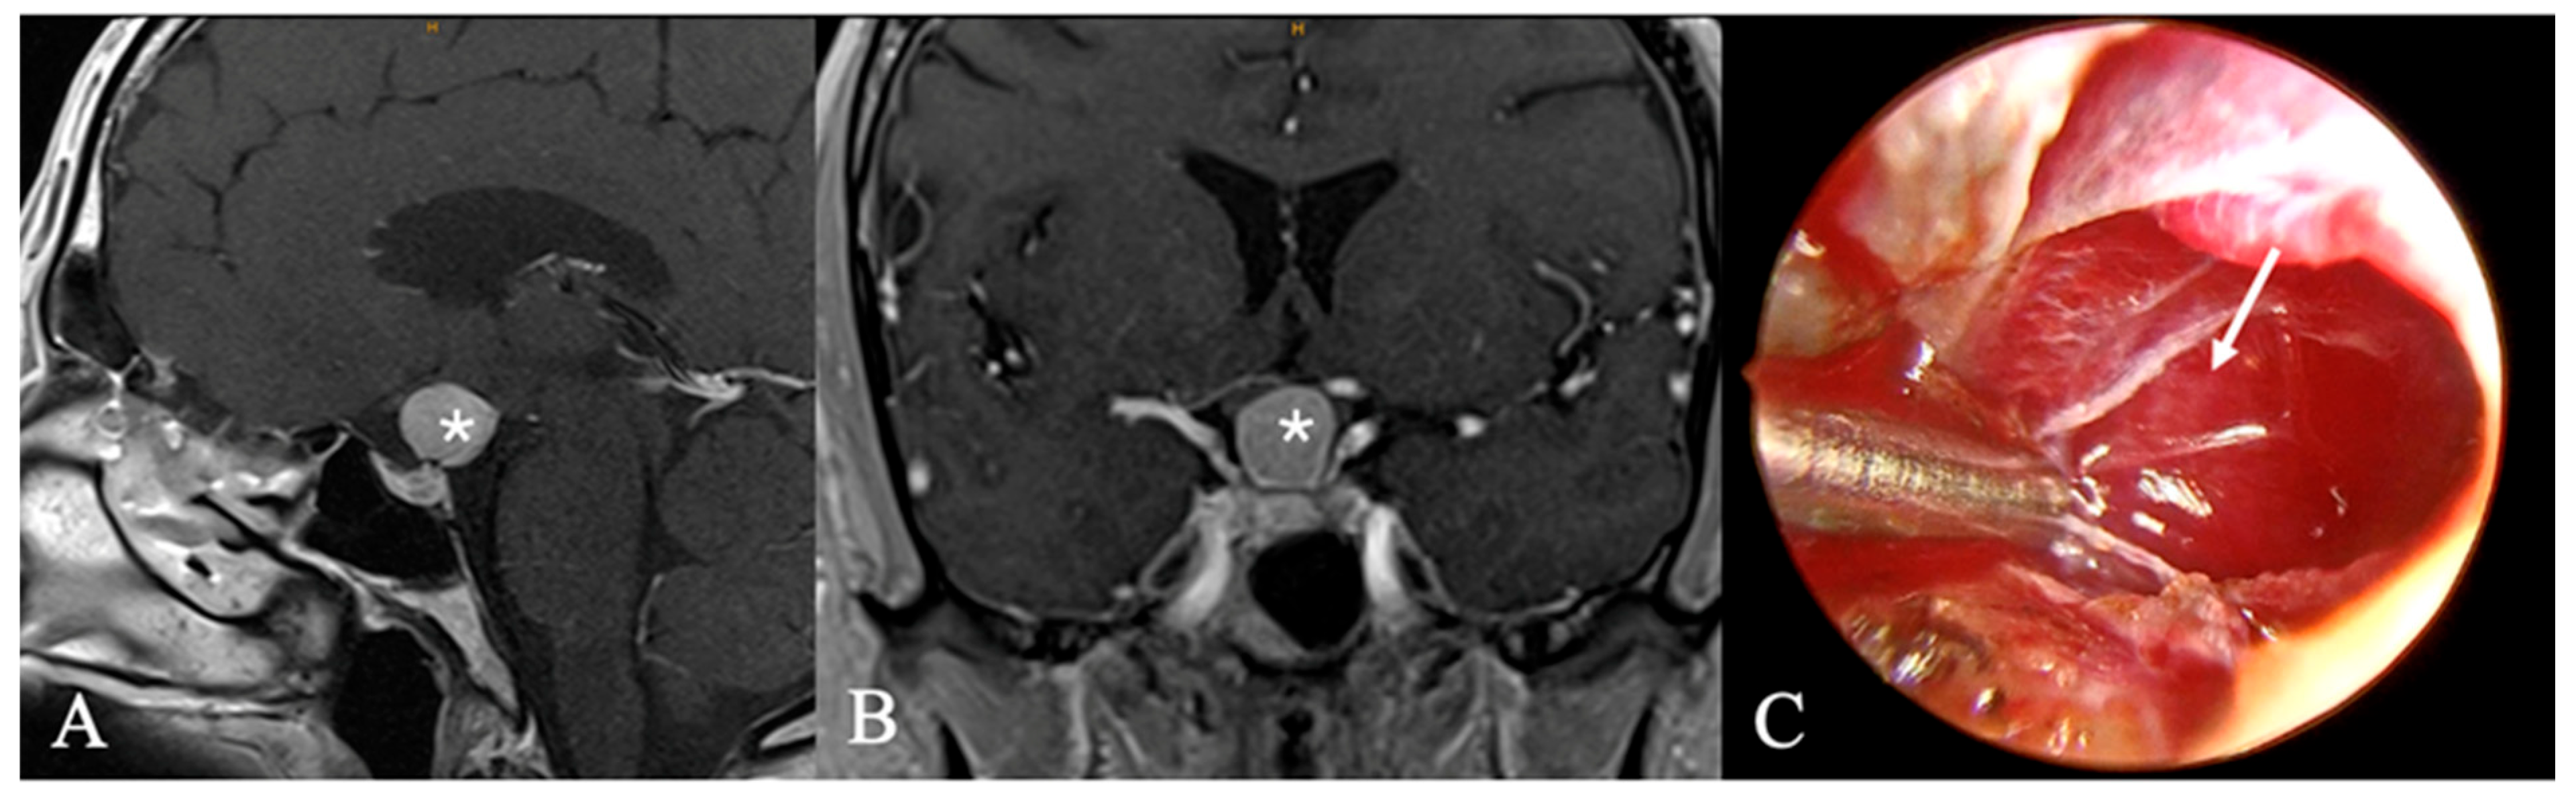

4.2. Differential Diagnoses and Case Presentations